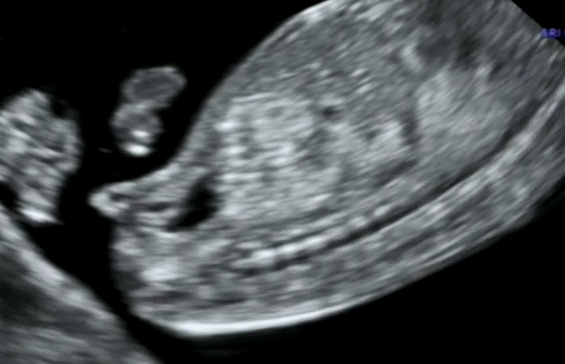

GIRL?

Hmm. Most likely. Is hat the only pic?

Yes I think hirl

Looks like a girl, congrats!

Girl